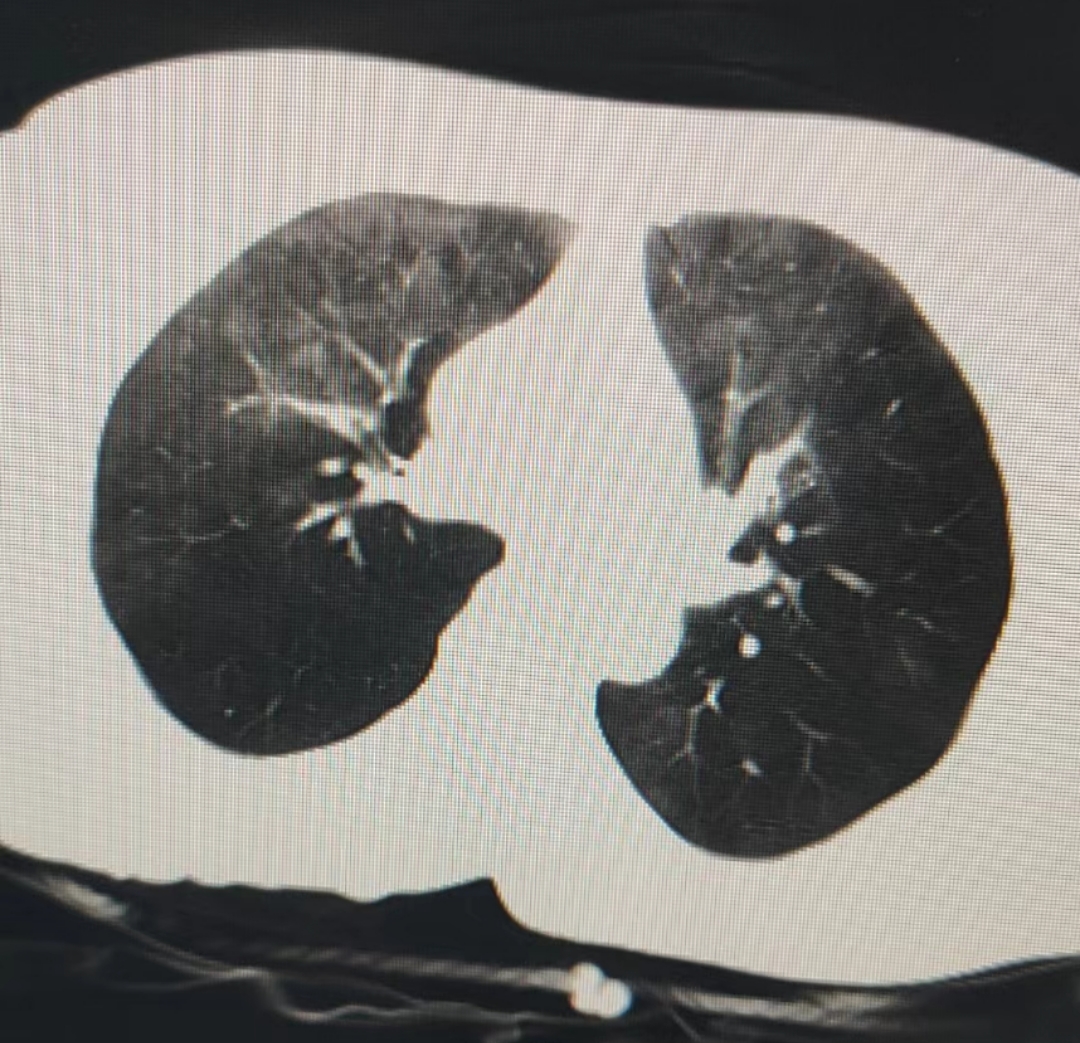

刚碰到个非常棒的客户,死状可以说是教科书级( ´∀`)

来无奖竞猜这是啥( ´∀`)

无标题 无名氏 2023-02-18(六)16:10:07 ID:Ezr71AX (PO主) [举报] No.55666460 管理

>>No.55666201

的确是肺,但不是一般的肺( ´∀`)

从这张肺片上推测一下死因呢゚ ∀゚)ノ

这是调了专门用来看肺的对比度,这个模式里除了气体剩下基本都是白的( ゚∀゚)

唯一的好消息是我们的那个疑难案子基本已经排除了刑事嫌疑,但病理结果出来之前死因还是不好说,而且有些敏感,所以暂时先按下不表还是说说那个肺ct的事吧( ゚∀゚)

所以那张肺CT里面的白色毛玻璃样阴影其实是肺泡里的水,白色的枝杈和小点是灌满水的支气管,这是一张非常标准的水性肺气肿CT,结合死者口鼻处的蕈样泡沫,手中抓握水草,上颌窦、气管腔、胃肠道里的大量液体影像判断,这是一个教科书般标准的溺死案例( ゚∀゚)